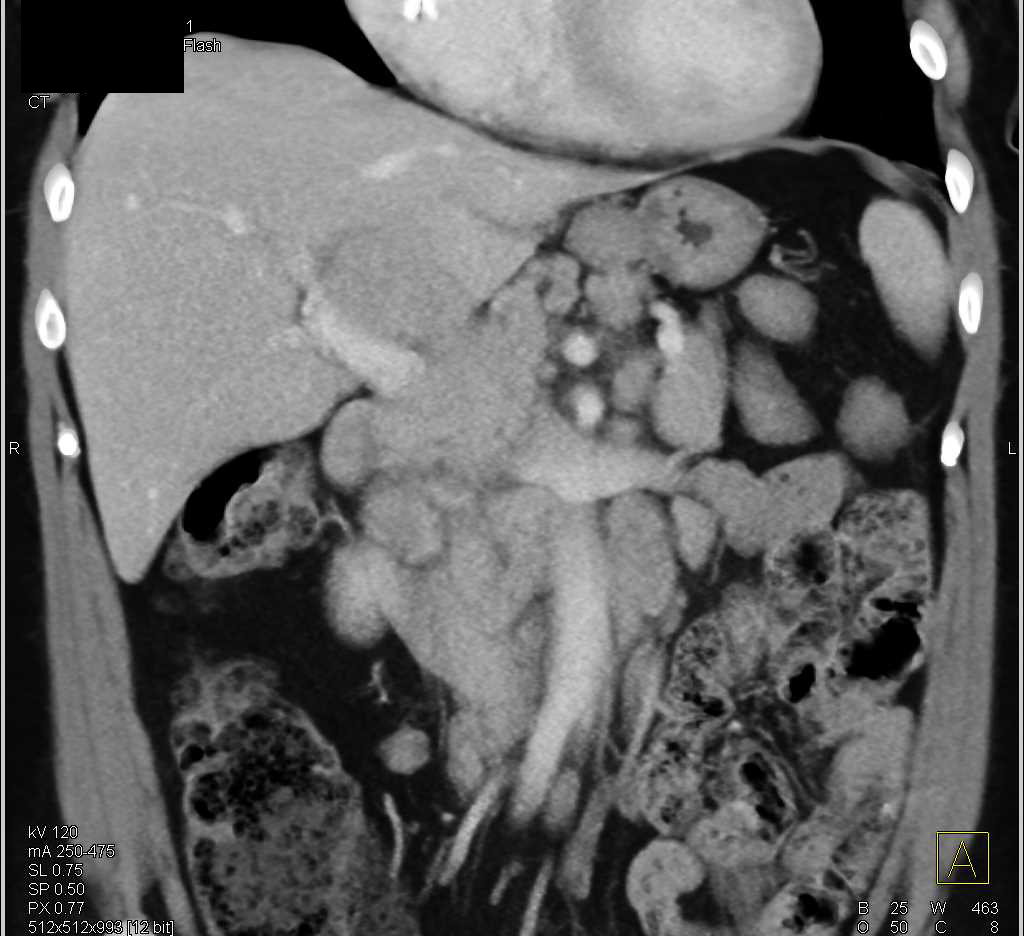

Carcinoma of the Head of the Pancreas with Dilated Pancreatic Duct